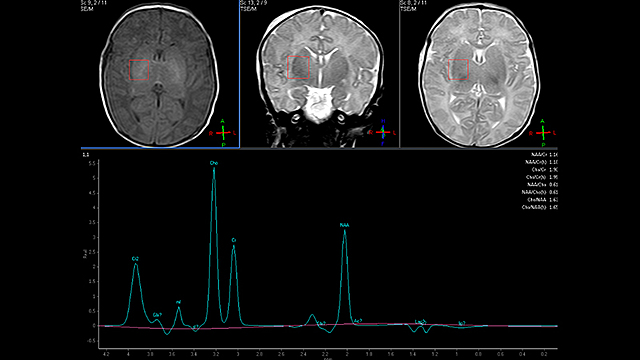

• La espectroscopía por RM

La espectroscopía por RM

Una nueva técnica de transformada de Fourier a la espectroscopía por RM. Utilizando la FID de Hahn, aumentando la razón señal/ruido además de abrir las puertas al análisis computacional de las señales, reduciendo significativamente el tiempo de registro.

La RM médica está demostrando una potencialidad insospechada de nuevos avances como la capacidad de realizar estudios funcionales, difusión, perfusión, tractografías, espectroresonancia,